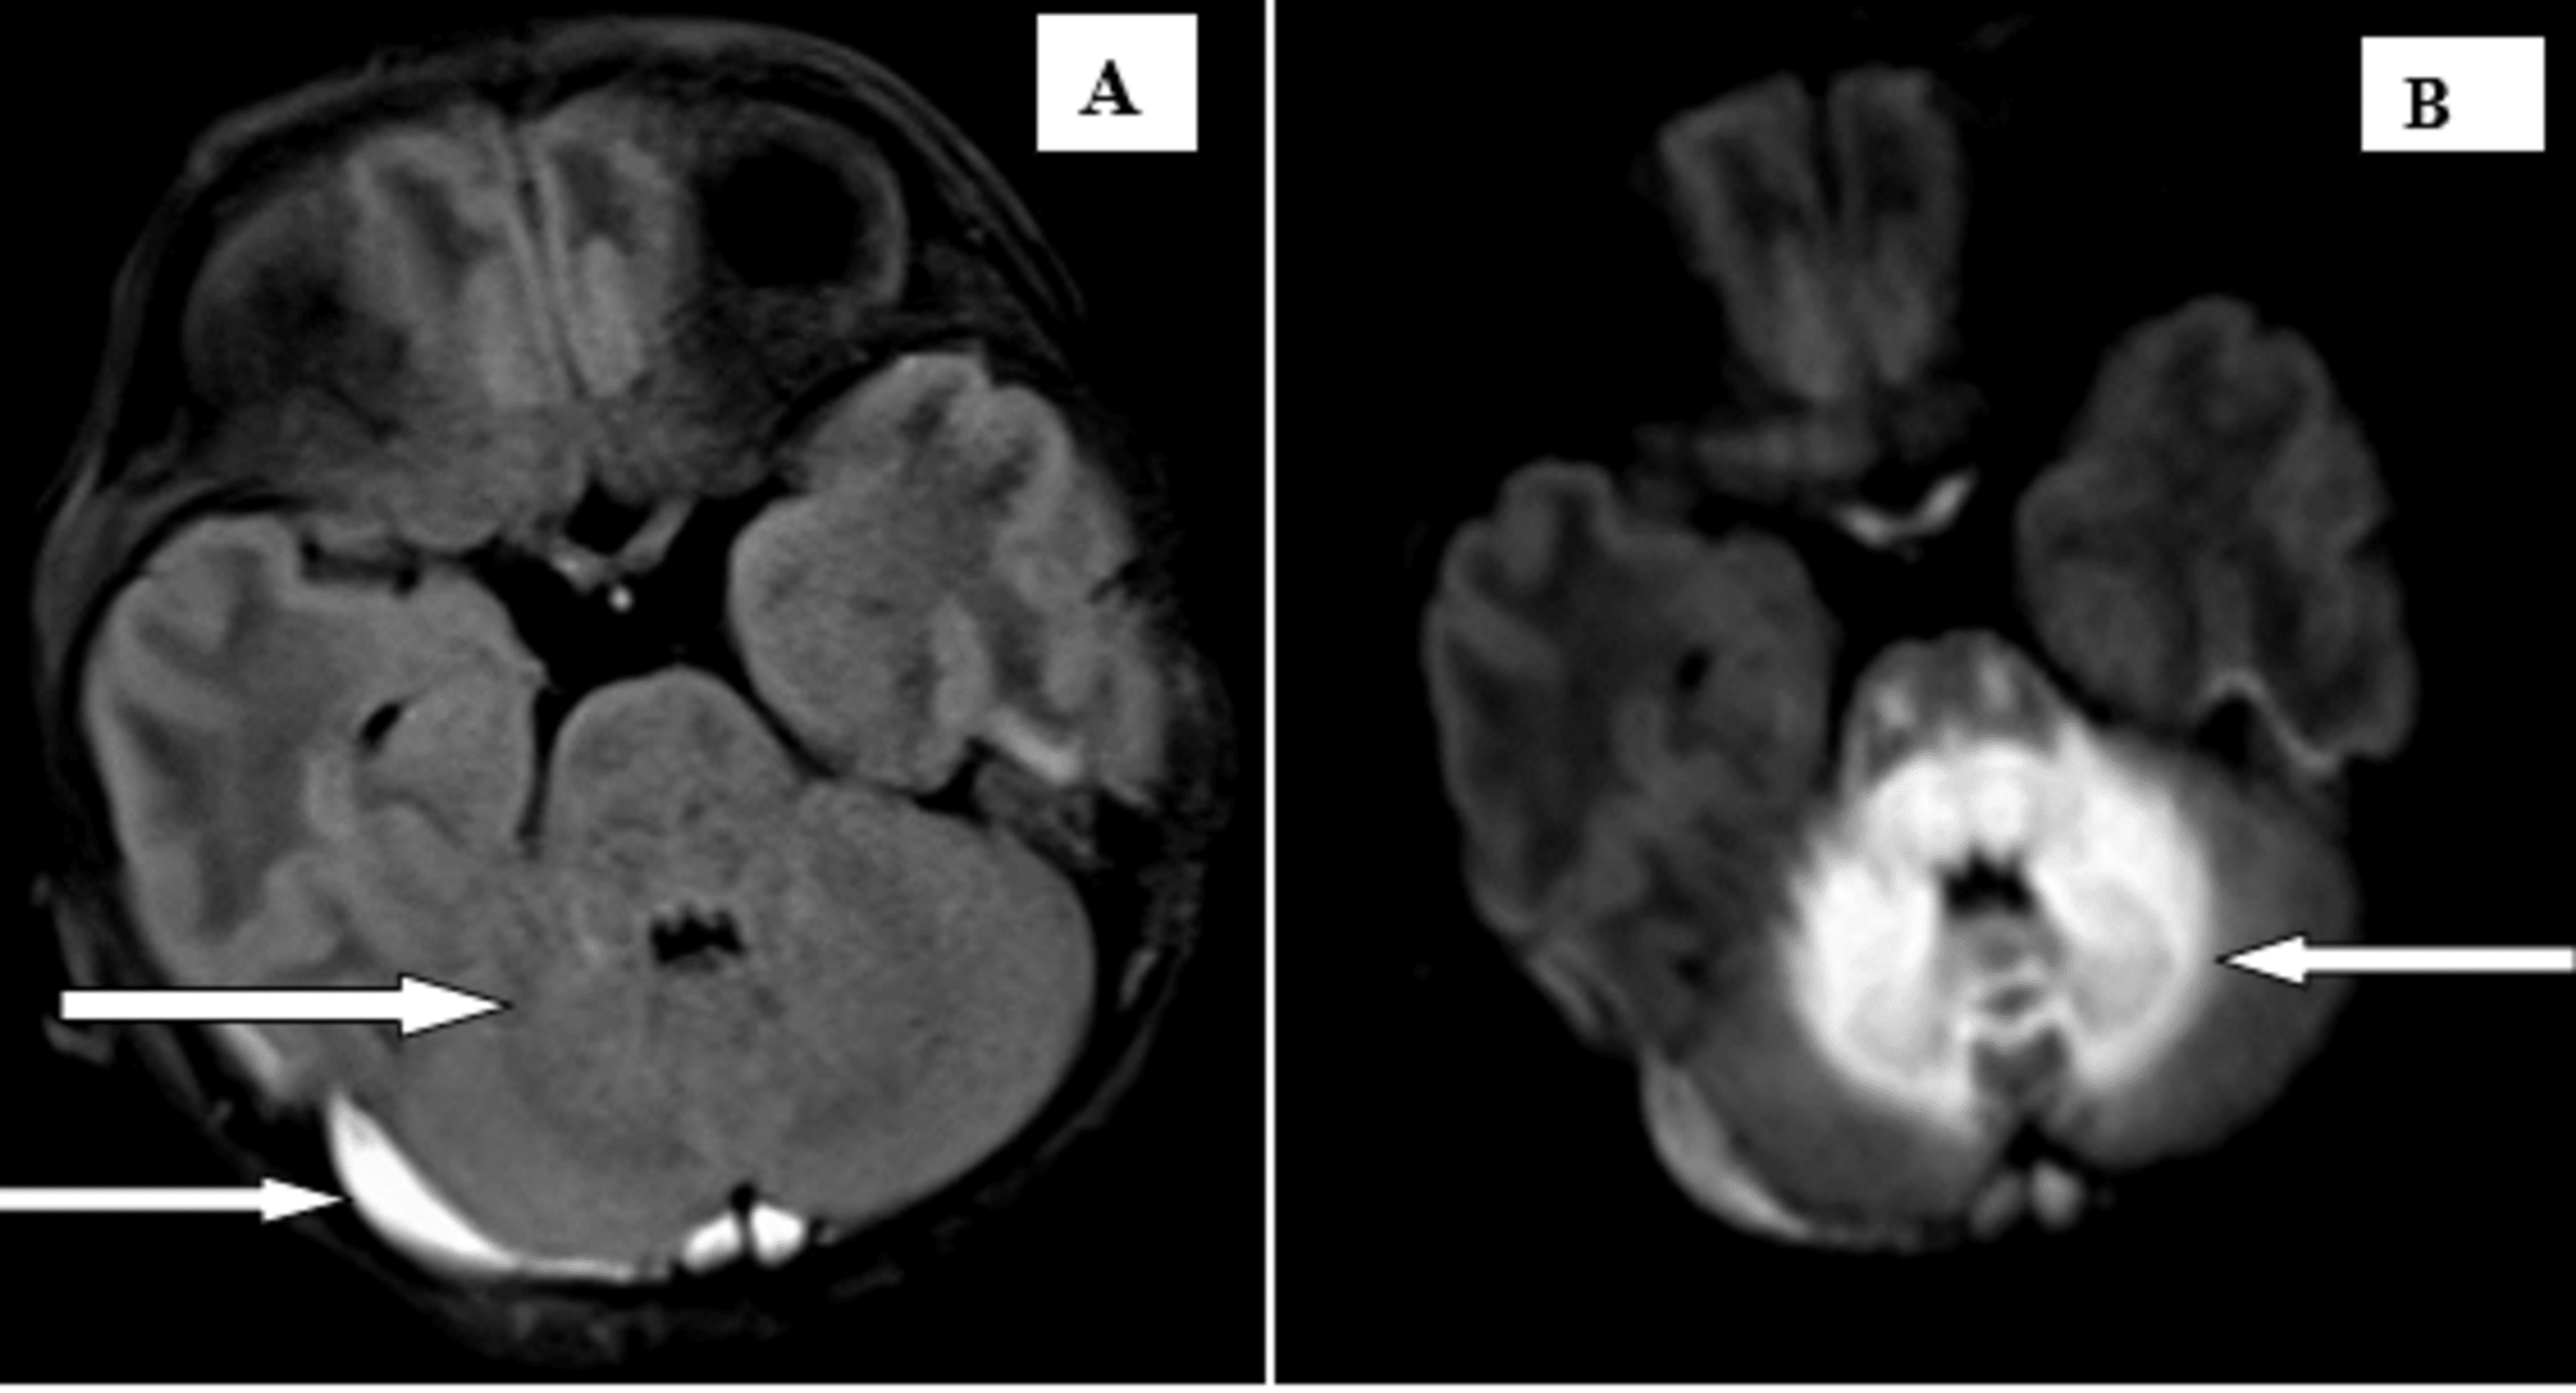

Brain resonance imaging findings and radiologic review of Maple Syrup Disease Seizures Classically, affected neonates present with feeding problems, vomiting, lethargy, and irritability, leading to seizures, coma, and. Classically, affected neonates present with feeding problems, vomiting, lethargy, and irritability, leading to seizures, coma, and. Classically, affected neonates present with feeding problems, vomiting, lethargy, and irritability, leading to seizures, coma, and. Here we describe a neonate with msud and a distinctive electroencephalogram (eeg). Maple Syrup Disease Seizures.